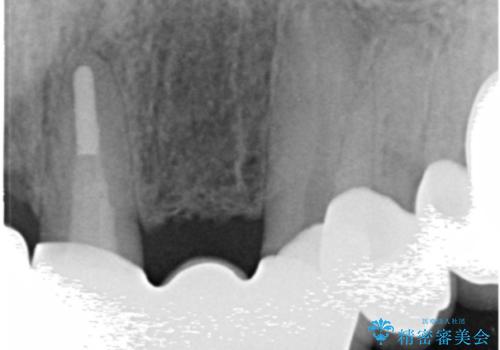

- 若い時に作った前歯のブリッジがの根元が黒くなってきているとのことで来院。

支える歯が1本虫歯がひどく、割れていました。

根の治療からやり直して新しいブリッジにしています。

ブリッジの支台歯は、根の再治療を含めて行なっています。